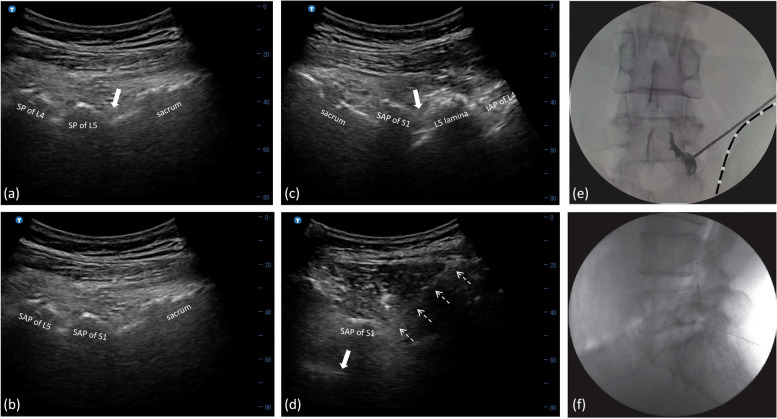

Methods: One-hundred and forty-one patients were retrospectively stratified into two groups based on the treatment they received: novel group, receiving US-guided and fluoroscopy (FL)-controlled TFEIs using a sagittal oblique approach between the superior articular process of L5 and S1, and control group, receiving US-guided TFEIs with conventional transverse approach combined with FL confirmation. Accuracy of contrast dispersing into lumbar epidural space was set as the primary endpoint. Radiation dosages, procedure time, numeric rating scale (NRS) scores, Modified Oswestry Disability Questionnaire (MODQ) scores, adverse events, and rescue analgesic requirement were also recorded. The generalized liner mixed model (GLMMs) was employed to compare the repeatedly measured variables between groups, taking individual confounding factors as covariance.